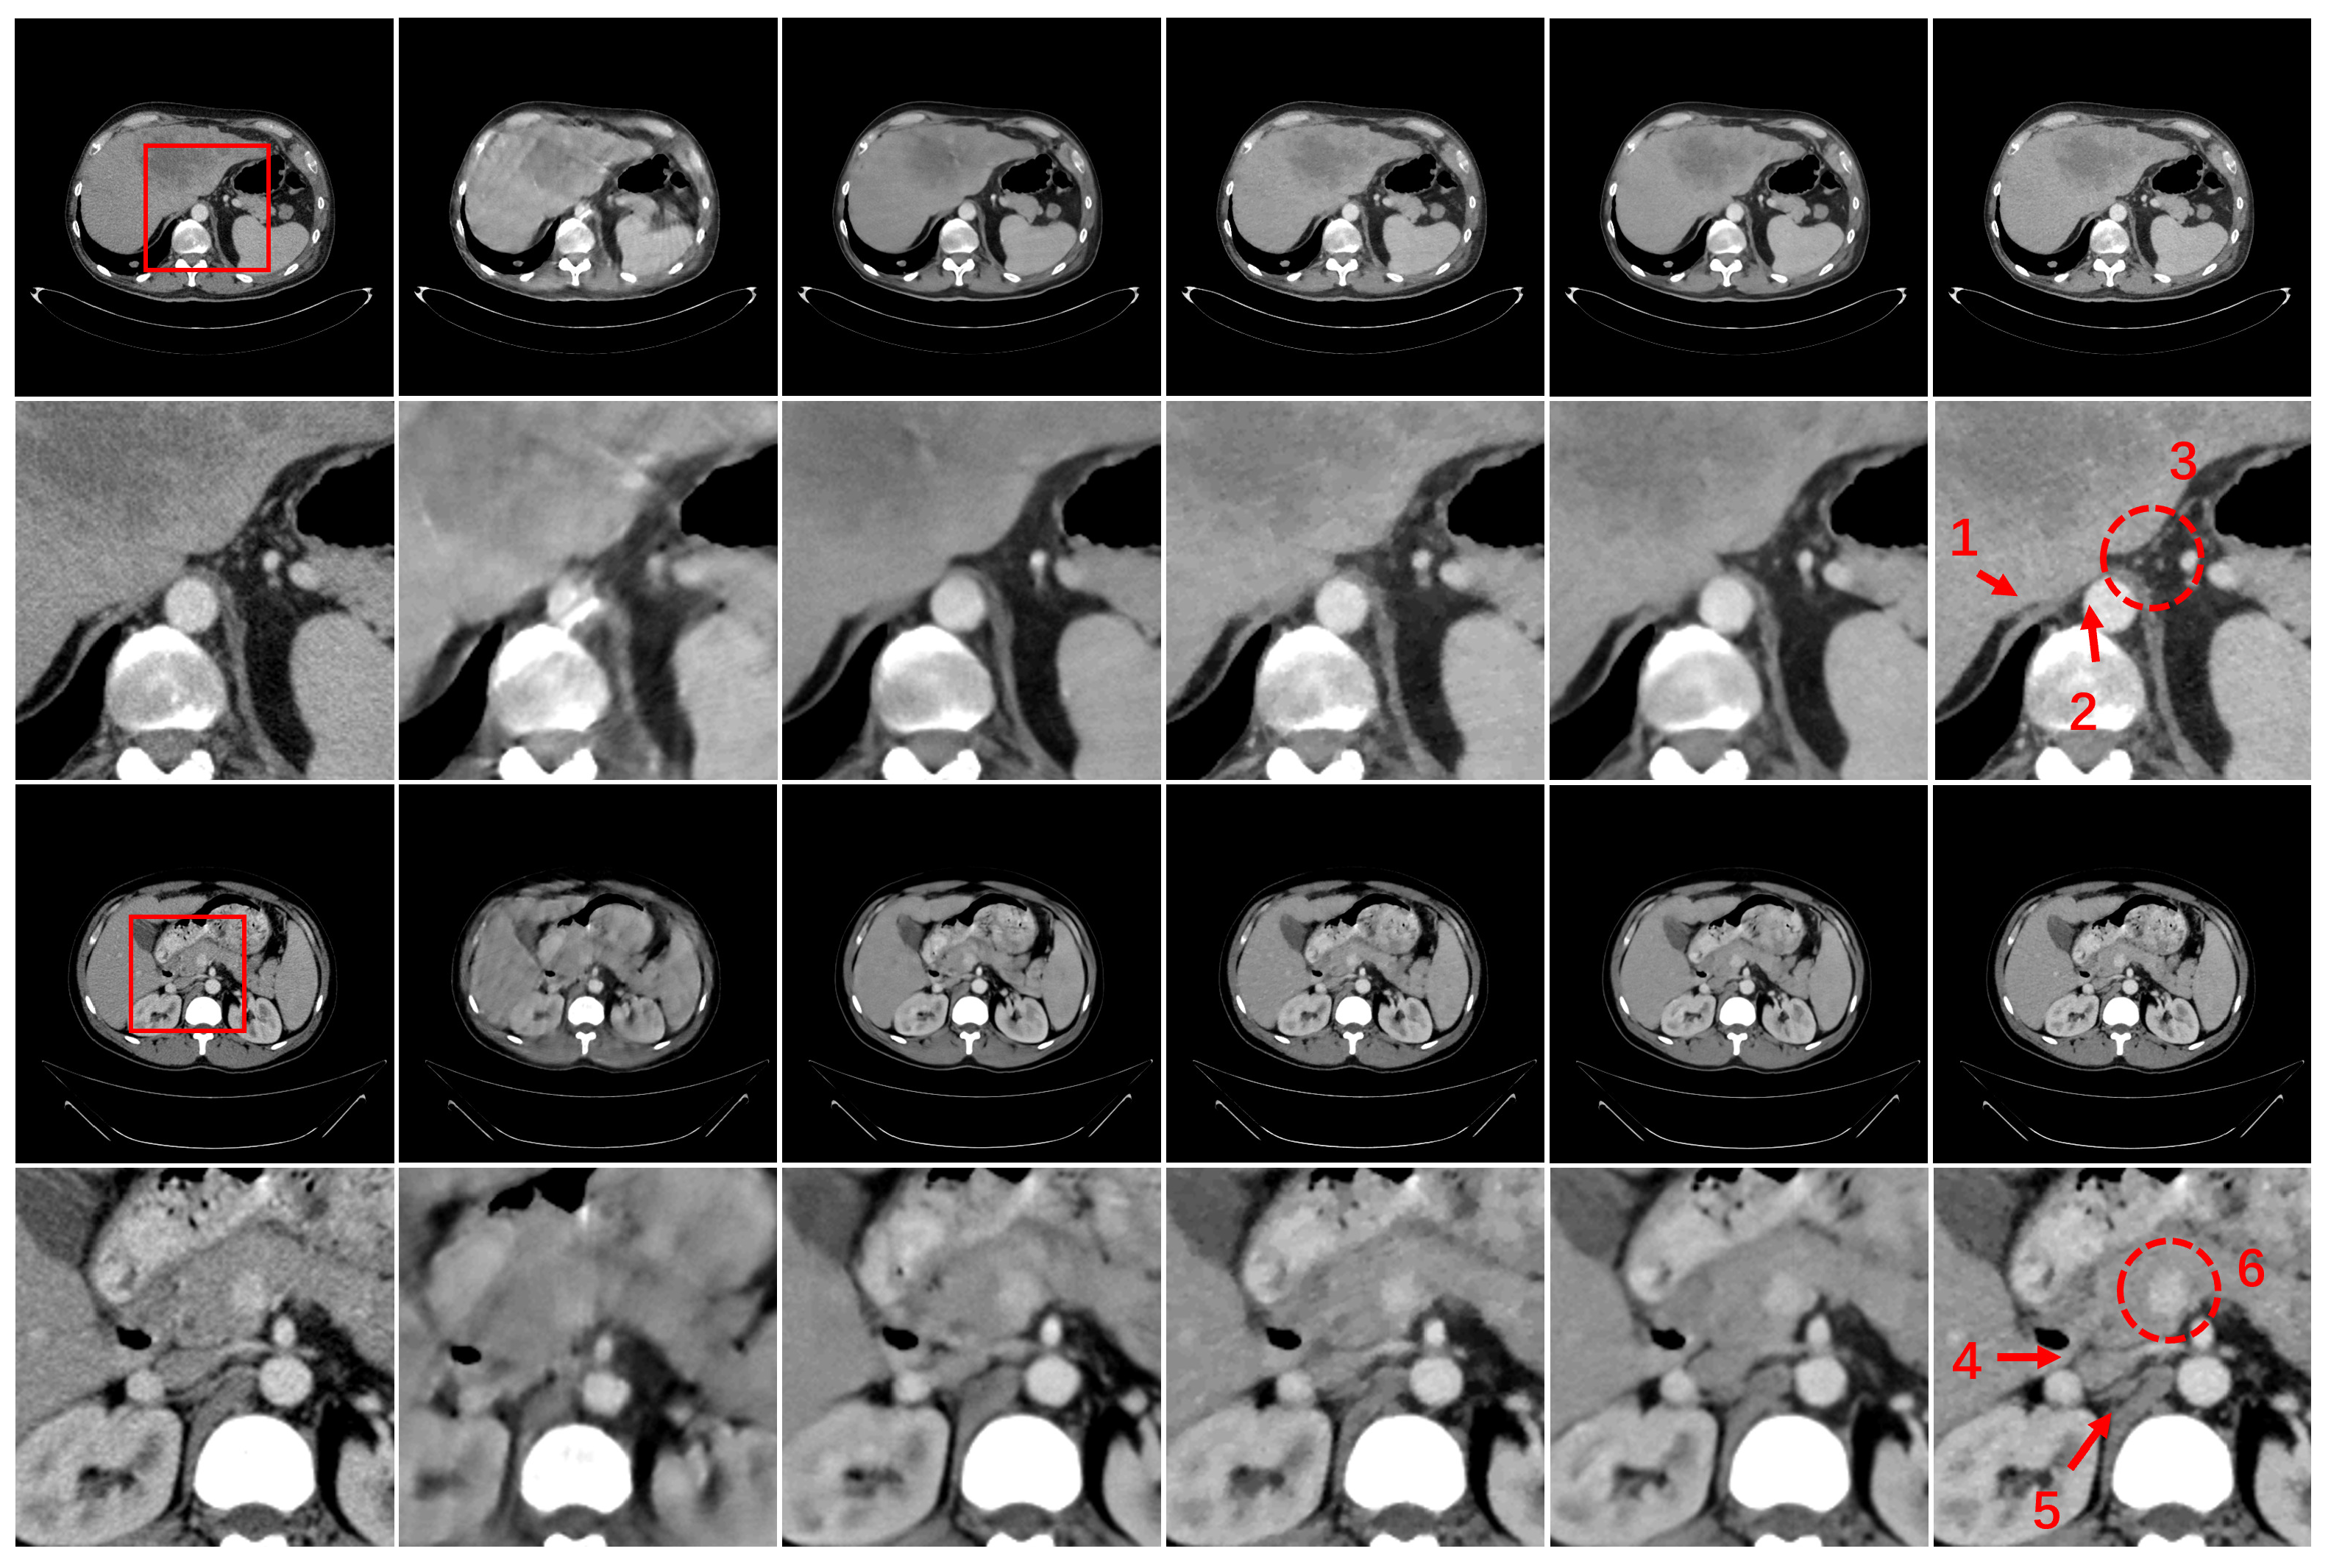

3.3. Results

3.4. Ablation Study